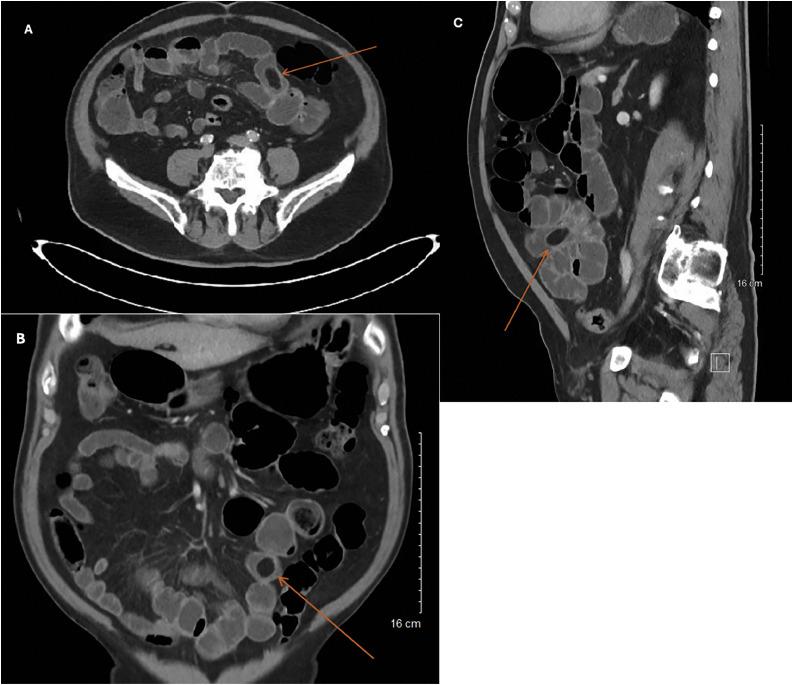

Gallstone ileus, a rare complication of cholecystitis, occurs when the distal ileum becomes obstructed by gallstone causing, mechanical bowel obstruction. Gallstone ileus with history of cholecystectomy is exceptionally rare, with few cases documented in literature. This case report details the discovery of a large, impacted gallstone 16 years postcholecystectomy. An 87-year-old male presented with progressively worsening right-sided abdominal pain over 2-3 days. Exploratory laparotomy unveiled a 2.0 cm × 2.5 cm gallstone was obstructing the terminal ileum. Patient improved remarkably postoperatively and was discharged with resolution of symptoms. A potential cause for this large gallstone impaction within the terminal ileum is gallstone ileus, which can be explained with history of intentional or unintentional subtotal cholecystectomy or long cystic duct remnant. Both rare occurrences that allow gallstone formation or passage through a chronic cholecystoduodenal fistula due to inflammatory changes. With increasing trend toward subtotal cholecystectomies and division of cystic duct closer to the gallbladder neck, this case could potentially be explained as a gallstone ileus, despite extended postoperative intervals.

摘要

胆石性肠梗阻是胆囊炎的一种罕见并发症,当远端回肠被胆结石阻塞导致机械性肠梗阻时发生。有胆囊切除术史的胆石性肠梗阻极为罕见,文献中记载的病例很少。本病例报告详细描述了胆囊切除术后16年发现的一枚巨大嵌顿胆结石。一名87岁男性在2至3天内出现右侧腹痛逐渐加重。剖腹探查发现一枚2.0厘米×2.5厘米的胆结石阻塞了回肠末端。患者术后明显好转,症状缓解后出院。回肠末端出现这种巨大胆结石嵌顿的一个潜在原因是胆石性肠梗阻,这可以用有意或无意的次全胆囊切除术史或长胆囊管残端来解释。这两种罕见情况都因炎症变化而导致胆结石形成或通过慢性胆囊十二指肠瘘管。随着次全胆囊切除术以及在更靠近胆囊颈部处切断胆囊管的趋势增加,尽管术后间隔时间较长,本病例仍可能被解释为胆石性肠梗阻。